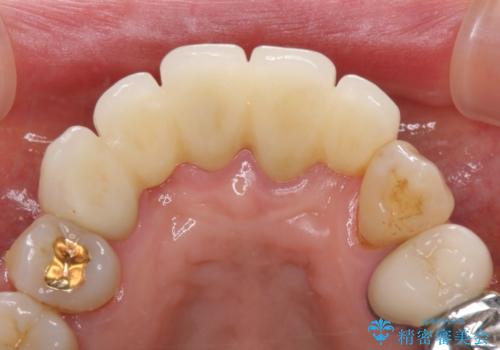

露出していた歯根や金属の縁が見えてしまい、なかなか口を開けて笑うことができなかったのですが、歯肉の位置に縁を合わせることで自然な仕上がりとなりました。

ブリッジの隙間にものが詰まったり、空気が抜けたりすることも無くなり、話しやすさも改善することができました。

露出していた歯根が覆われるため、歯冠が長く見えてしまうことが懸念されましたが特に気になることはなく、患者様には大変満足していただきました。